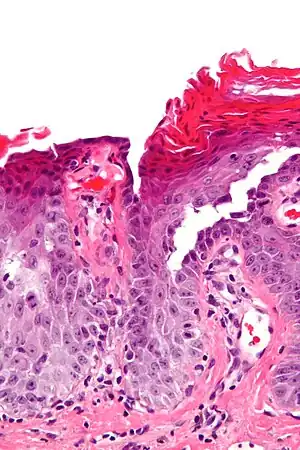

| Micrograph of transient acantholytic dermatosis, showing subcorneal separation and acantholysis. H&E stain. | |

It is characterized histologically by acantholysis,[3] with or without dyskeratosis.[4] Once confirmed, most cases of Grover's disease last six to twelve months, which is why it was originally called "transient". However it may last much longer. Nevertheless, it is not to be confused with relapsing linear acantholytic dermatosis.

Grover's may be suspected by its appearance, but since it has such a characteristic appearance under the microscope a shave skin or punch biopsy is often performed.